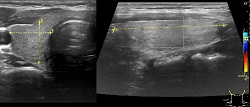

Ultarsonograf to bardzo cenne narzędzie w diagnostyce wielu zaburzeń organizmu. Wykrywa choroby jamy brzusznej, szyi, naczyń krwionośnych, układu mięśniowo-szkieletowego i inne.